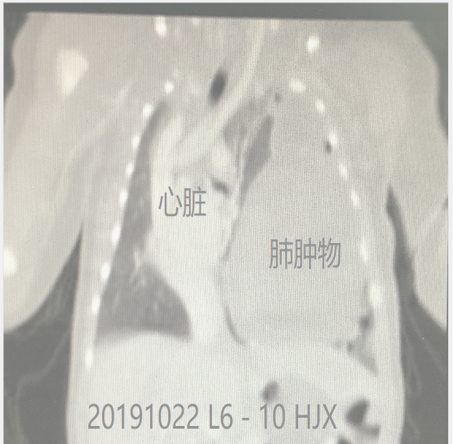

我结合一下我院的情况,正如上一篇所说,我院2018年接诊的86名肺囊性疾病的患儿,大部分选择1岁前进行手术,严重的肺炎确实是造成急诊手术、增加手术难度、增加术中患儿呼吸衰竭的危险因素,今年上半年我院的手术儿童平均年龄是5个月11天,最小的宝宝是2个月03天的宝宝。而今年的10月底更是为一名出生仅4天的宝宝进行了胸腔镜下的左下肺肿物切除术,也是因为重症的肺炎、呼吸衰竭而加重了手术难度。还好所有的宝宝们都恢复良好。